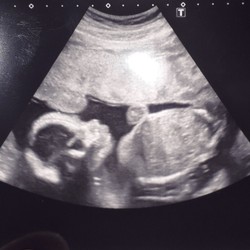

Ik heb dat schijnbaar ook. De echoscopiste vertelde dat dat een symptoom kan zijn dat er iets met de nieren of het hart is. Dat heeft ze goed nagekeken en dat is uitgesloten. Hey Kan ook een symptoom zijn van het syndroom van down. Gelukkig was bij ons de nipt test oke. Vroeger dachten ze dat het te maken kon hebben met een groeiachterstand maar daar zijn ze ook op teruggekomen...Hoeft dus helemaal niets te betekenen.

Verloskundige wil toch graag dat ik nog een extra groei echo krijg met ik dacht 33 weken.

En de linker nier lag trouwens ietsjes lager dan normaal maar dat zou ook geen probleem zijn.. dus misschien een teken daarvoor......????

Bij mij kwam precies hetzelfde uit de 20 weken echo.

Ik ben toen doorgestuurd naar het radboud, dat is standaard. Zij hebben nogmaals alles uitgebreid gecheckt en ze zagen geen afwijkingen. Het kan geen kwaad je kunt prima met 2 vaten I.p.v. 3 gaven zij aan! 鈽猴笍

Ik heb een extra onderzoek gehad in umc amsterdam. Bleek dat me jongen een hoefijzer nier heeft. Vandaar de 2 vaten. Kan geen kwaad. Blijkt dat half nederland er mee loopt maar niet eens weet. Wel naar een nier specialist en na de geboorte goed in de gaten houden met plassen.